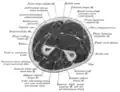

Cross-section through the middle of upper arm -

Cross-section through the middle of the forearm -